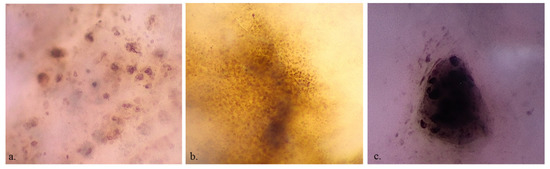

MMs more frequently showed roundish (36 (49.3%) vs. 35 (29.9%); p = 0.011), dendritic (22 (30.1%) vs. 19 (16.2%); p = 0.037), irregularly arranged (30 (41.1%) vs. 19 (16.2%); p < 0.001), and irregular in shape and size melanocytes (38 (52.1%) vs. 21 (17.9%); p < 0.001), and angled nests (16 (22.2%) vs. 9 (7.7%); p = 0.008) than nevi (Figure 2). Benign lesions more frequently revealed a network with edged papillae than MMs (30 (25.6%) vs. 3 (4.1%); p < 0.001) (Figure 3). Cell color (black 13 (11.1%) vs. 7 (9.6%), brown 107 (91.5%) vs. 66 (90.4%), violet/blue 45 (38.5%) vs. 29 (39.7%)), out-of-focus bluish (36 (30.8%) vs. 24 (32.9%))or grey/brown (23 (19.7) vs. 11 (15.1%)) structureless areas and vessel presence (26 (22.2%) vs. 23 (31.5%)) were not statistically significant for the differential diagnosis between MM and benign lesions. The observation of benign lesions showed a higher visibility of keratinocytes (109 (93.2%) vs. 64 (87.7%)) and roundish nests (42 (35.9%) vs. 22 (30.1%)) and a lower presence of melanophages [(19 (16.2%) vs. 17 (23.3%))] with no statistically significant difference.

Figure 2. ×400 dermoscopy shows pleomorphic roundish and dendritic melanocytes (a), homogeneous keratinocytes (b) and a cluster of melanocytes (c).